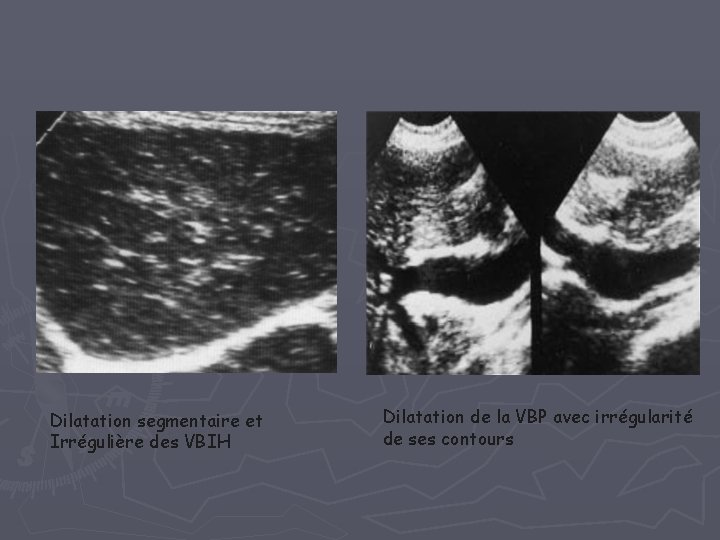

B- Cholangites sclérosantes = Atteinte inflammatoire chronique fibrosante et oblitérante des VBI et EH - Mdie idiopathique a – primitive: - origine auto-immune ( Svt RCH + ) - Homme , 30 -50 ans - Clinique : ictère Choléstatique d’installation insidieuse - ECHO + TDM : = Anomalies segmentaires et non systématisées • épaississement pariétal nodulaire ou régulier • dilatations et sténoses localisées et étagées : aspect en perles enfilées • calculs intra hépatiques

Dilatation segmentaire et Irrégulière des VBIH Dilatation de la VBP avec irrégularité de ses contours